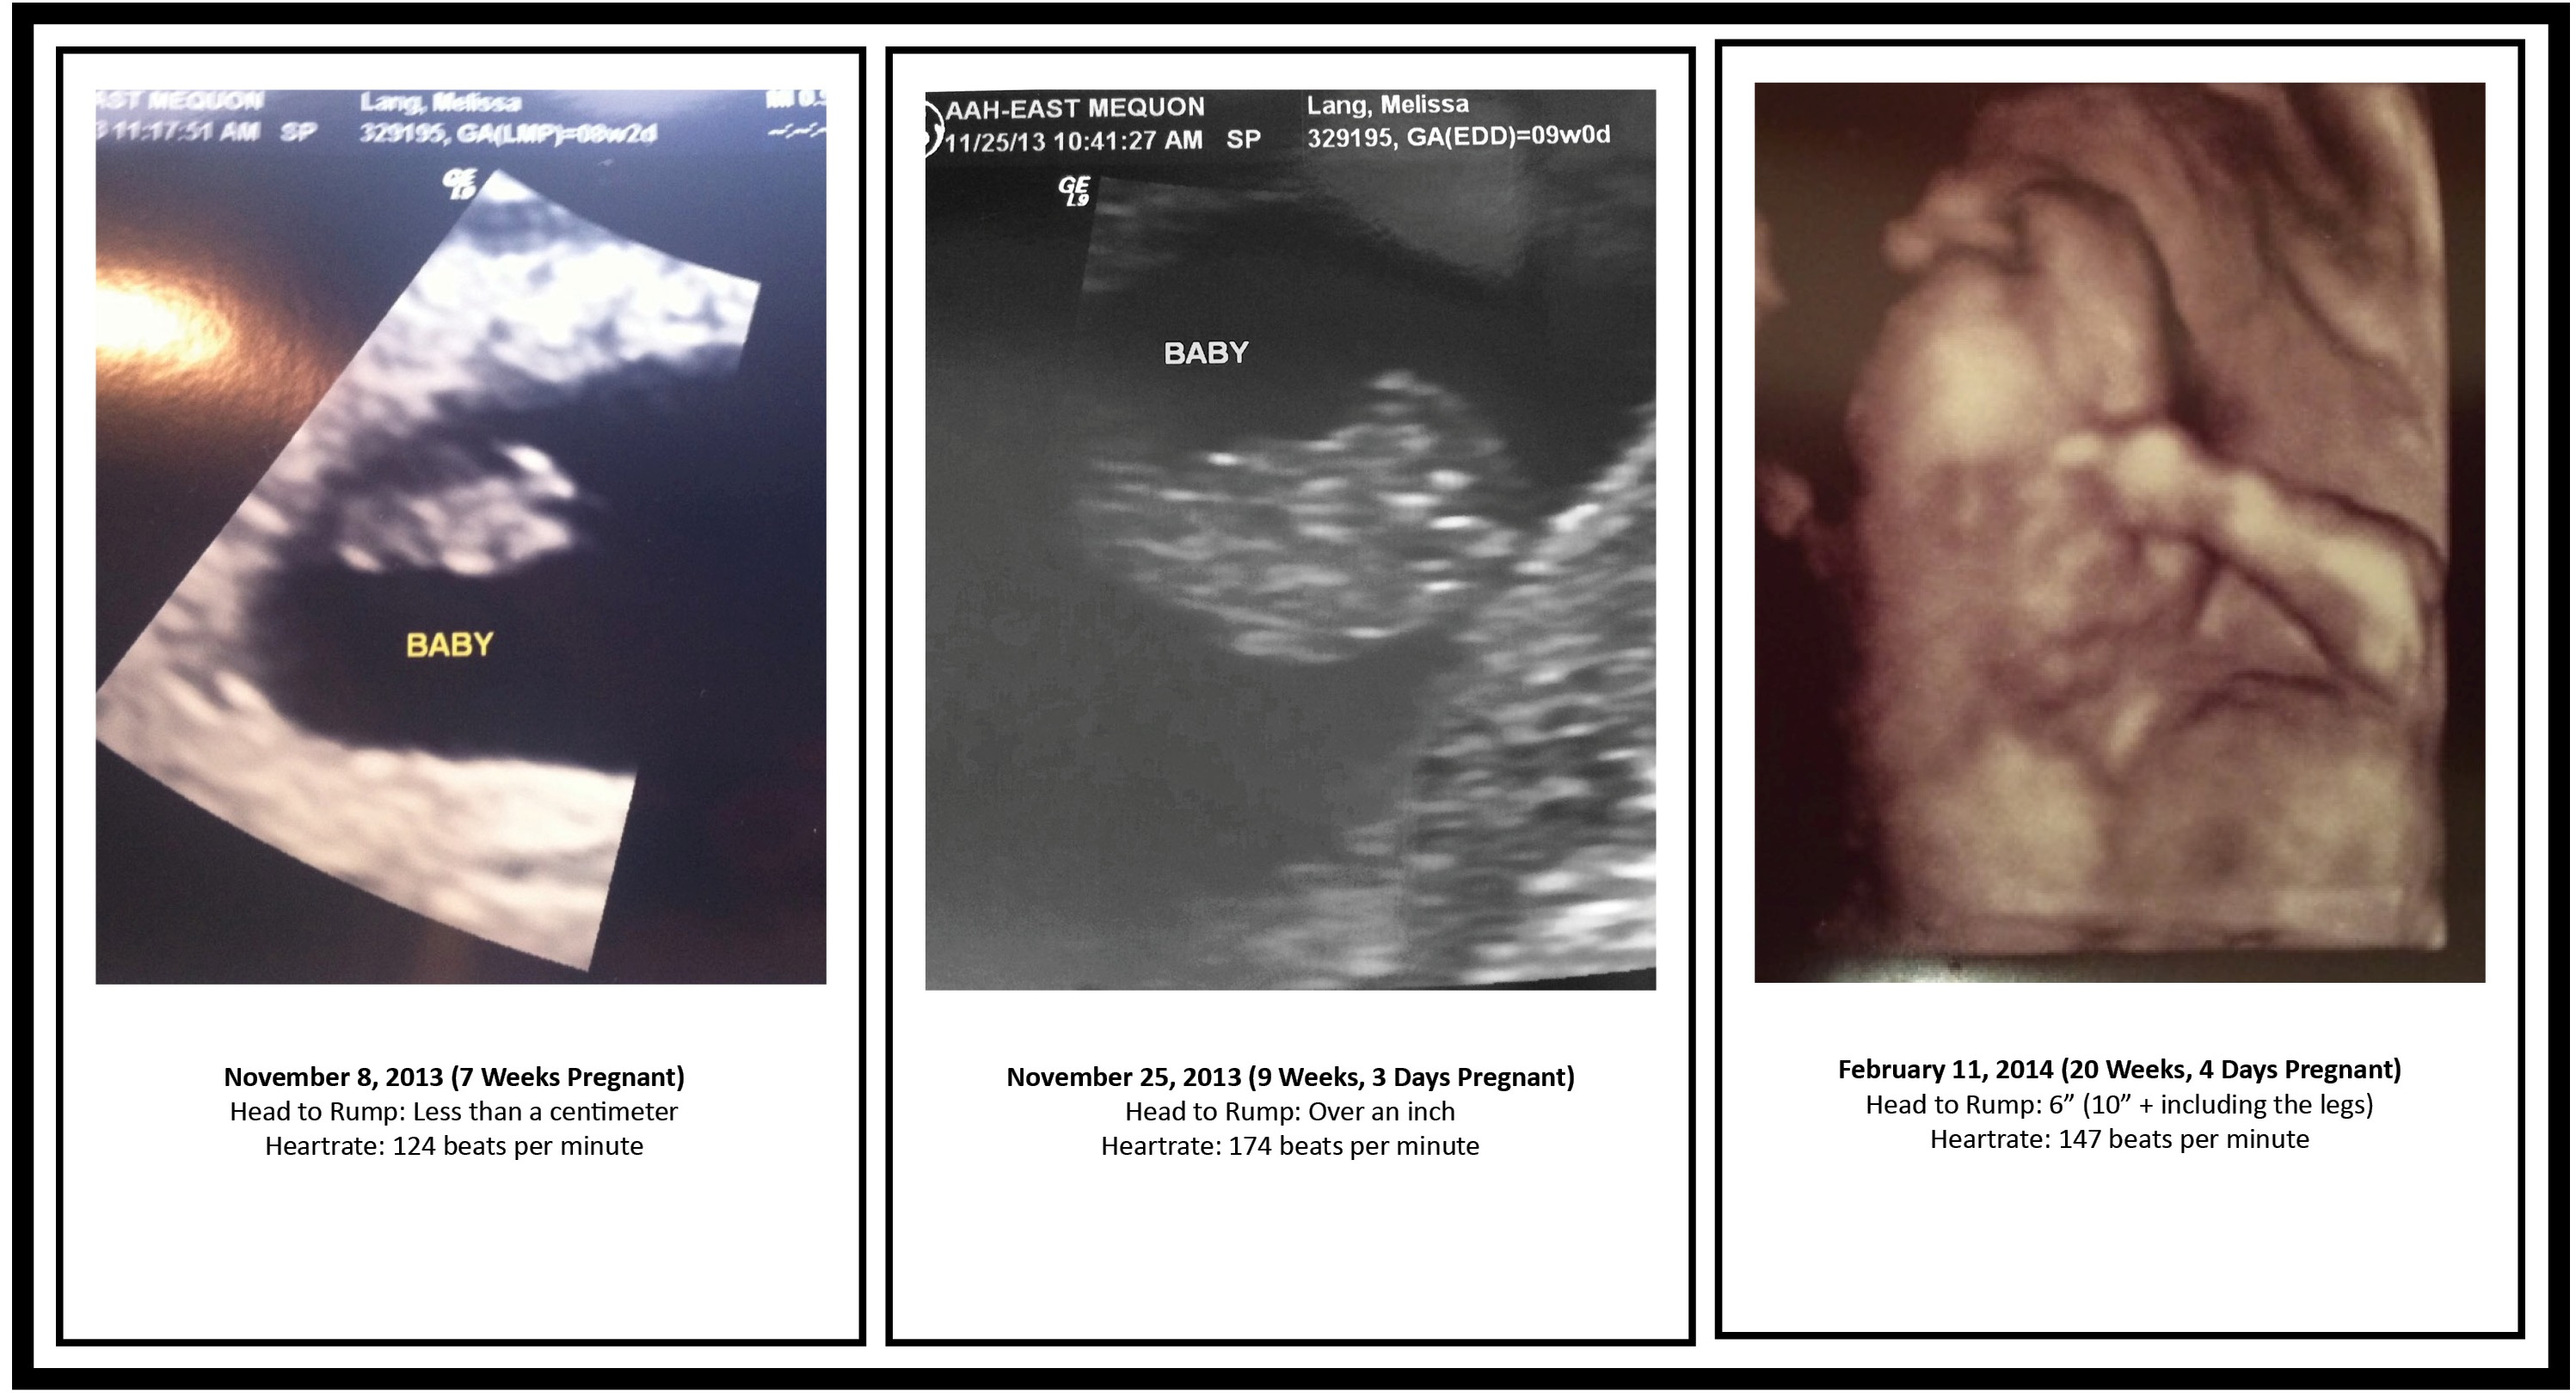

Here are the pics…

It’s crazy what can happen in 11 weeks! Check out the growth since our last ultrasound!